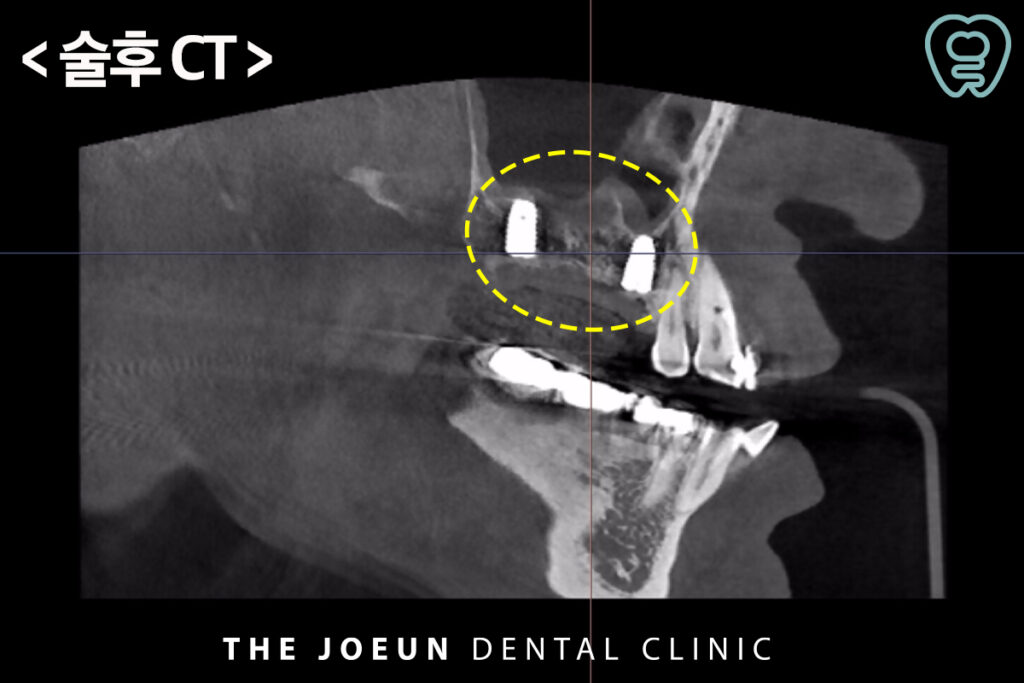

식립 약 4개월 뒤 최종 보철물까지 완료하였습니다.

이 방법은 남은뼈가 3mm 이상인 경우 상악동을 상방으로 거상시키면서 골이식과 임플란트 식립을 동시에 진행할 수 있는 방법을 말하는데요. 수술 시간이 길지 않고 수술 후 붓기와 통증이 상대적으로 적다는 장점이 있습니다. 또한, 환자분들의 수술 후 불편감을 줄여드릴 수 있으며 부작용 및 통증도 줄일 수 있습니다.

저희 다사치과 강창더좋은에서는 정밀한 진단을 위하여 3차원적 분석이 가능한 3D CT 장비를 활용하여 구강 구조를 면밀하게 파악하여 치료 계획을 수립하여 꼼꼼하고 섬세한 진행 과정과 치료가 종결되었다고 해서 끝나는 것이 아닌 체계적인 사후관리 시스템까지 갖추어 수준 높은 진료가 가능합니다. 항상 환자분들을 위해 연구하고 노력하겠습니다. 감사합니다!